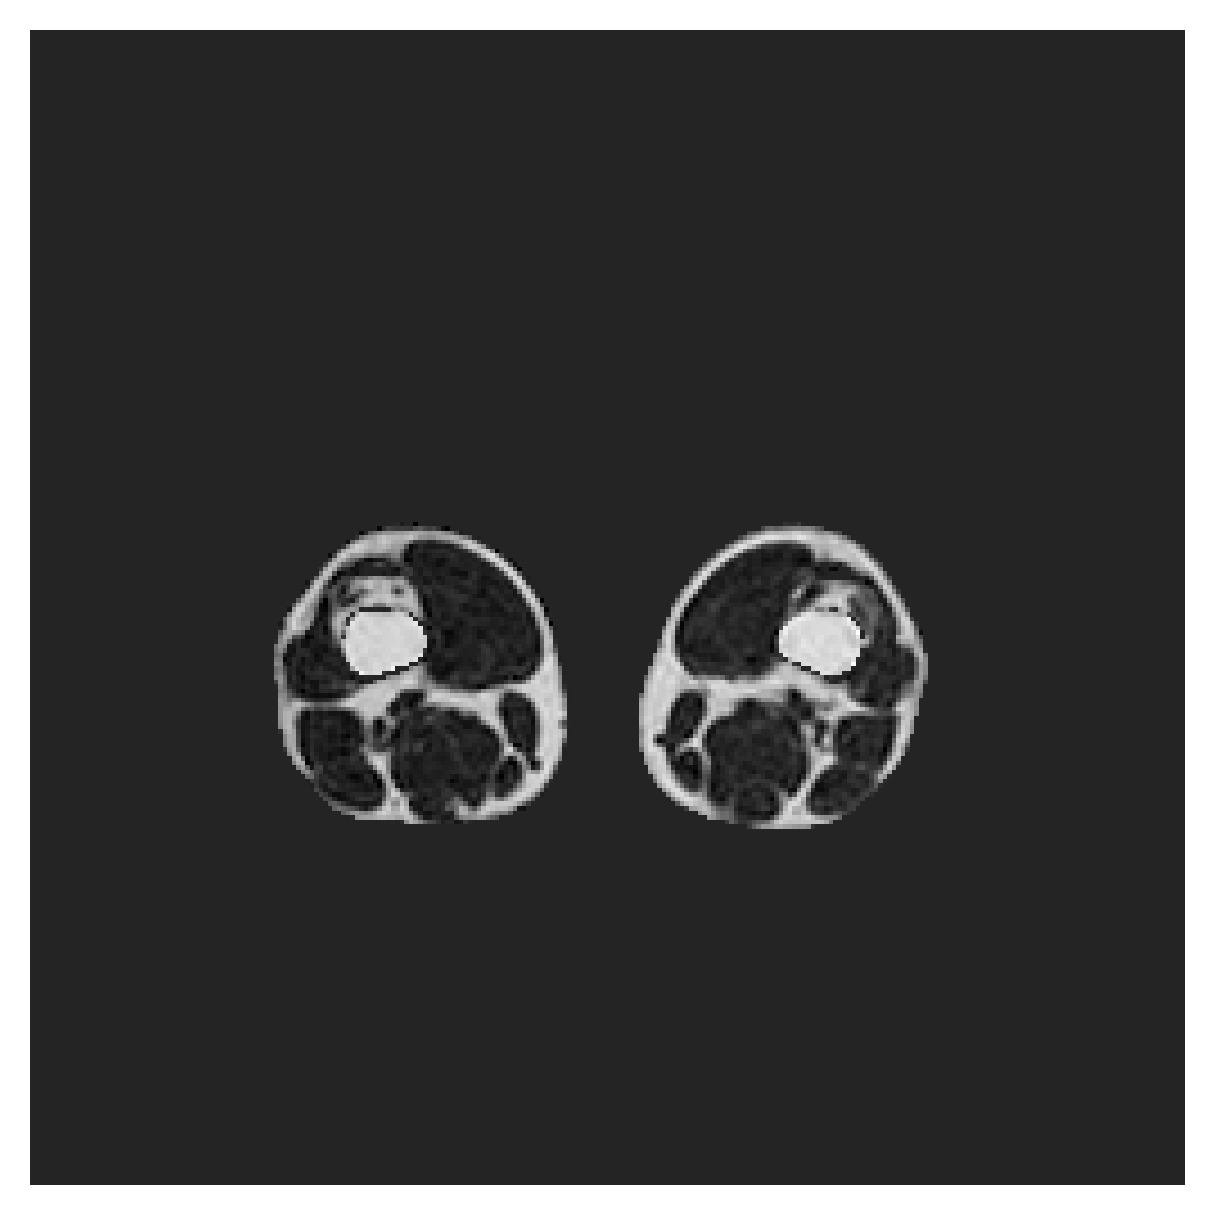

([5]) The Automated Cardiac Diagnosis Challenge (ACDC) is a public benchmark multi-class heart segmentation dataset. It contains cine-MR images of 150 patients (of which 100 are available for training and the rest 50 comprise a test set), covering healthy scans and four types of pathologies in equal amounts, with annotations for the right ventricle (RV), myocardium (Myo) and left ventricle (LV) heart structures. We split the training set randomly, using 65 subjects for training, 10 for validation and 25 as a hold-out test set. Due to the large and varying interslice gap, we work with 2D slices instead of 3D volumes directly. This includes distance map computation.

The Prospective investigation of Obesity, ENergy production and Metabolism (POEM) is a local (not currently publicly available; PI: L. Lind, see [22] for details) cohort of whole-body fat/water separated MR images. Full annotations of the liver, kidneys, bladder, pancreas and spleen are available for 50 subjects, providing a challenging segmentation dataset with heavily imbalanced classes of varying shapes. The resolution of the data is anisotropic, with reconstructed voxel size of in left-right, anterior-posterior and foot-head directions, respectively. For additional technical details regarding the acquisition and specifications of the images see [22].